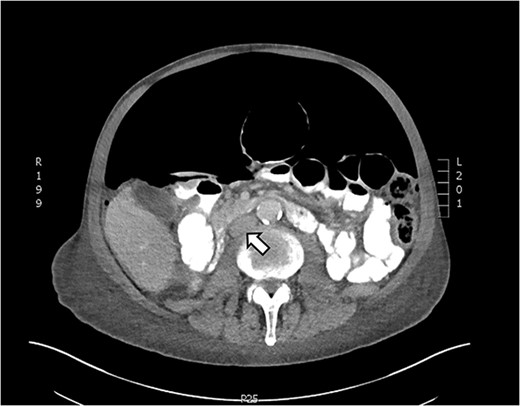

Axial CT showing tension pneumoperitoneum and collapsed inferior vena cava (arrow)

Here, we present a case of spontaneous idiopathic pneumoperitoneum with CT findings of tension pneumoperitoneum managed successfully with bedside decompression using a pig-tail catheter attached to a chest drain. Failure of decompressing the tension pneumoperitoneum may result in hemodynamic instability and ischemia of abdominal organs as large pneumoperitoneum may compress on the inferior vena cava reducing venous return to the heart. CT findings of tension pneumoperitoneum include marked elevation of diaphragm, decreased thoracic volume and/or compression of the inferior vena cava [10]. Emergency percutaneous needle compression using 16G cannulas have been used in cases for immediate decompression of the tension pneumoperitoneum [11]. Our patient had a high POSSUM score; for him to undergo a laparotomy would place him at a high mortality and morbidity risk. Here we demonstrate successful management of idiopathic tension pneumoperitoneum with pig-tail catheter attached to an intercostal drain.